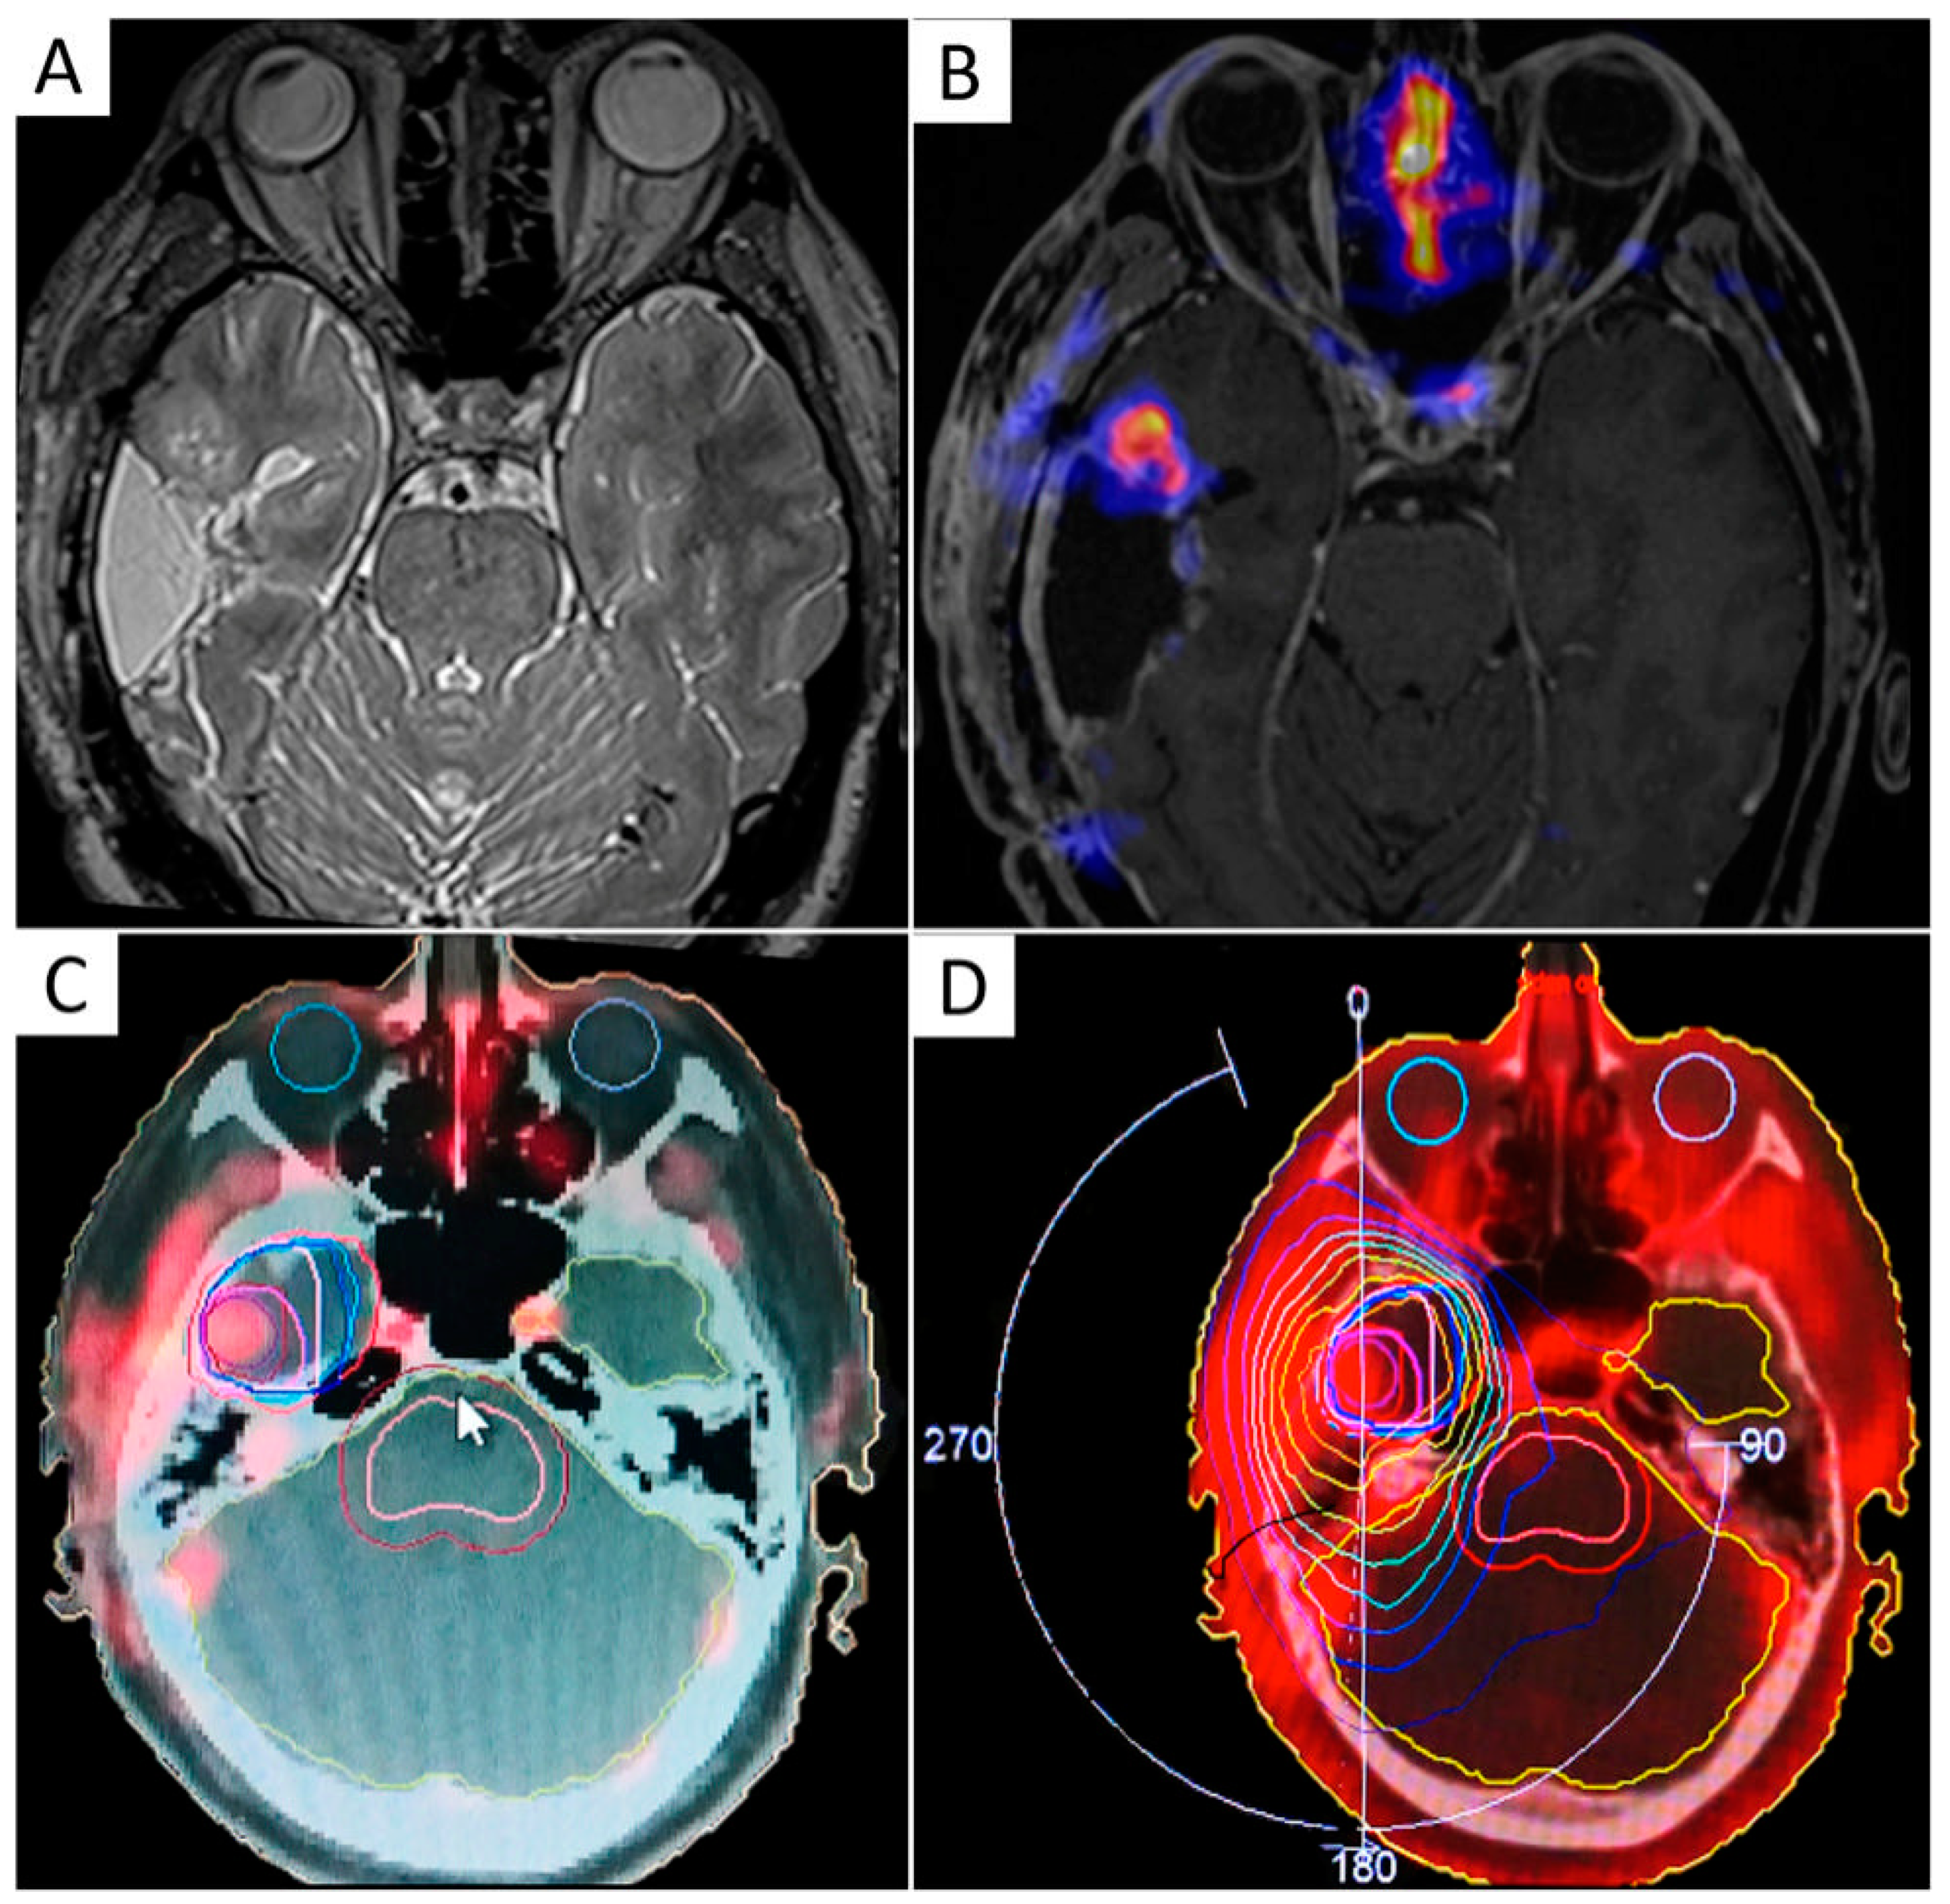

Figure 4.

Example of a volumetric modulated arc therapy (VMAT) sequential boost of radiation to hypoxia-positive recurrent GBM. T2-weighted and contrast-enhanced T1-weighted MRI sequences were acquired along with 64Cu-diacetyl-bis(N4-methylthiosemicarbazone) (ATSM) PET on a hybrid 3T PET/MR scanner, three hours after radiopharmaceutical injection (A,B). 37.5 Gy were delivered in 15 daily fractions to the surgical cavity followed by a boost of radiation (5 Gy) to the 64Cu-ATSM-positive tumor region, indicating chronic hypoxia (C,D).